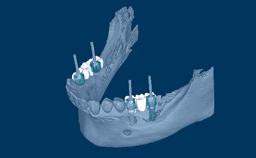

A implantodontia evoluiu consideravelmente desde os protocolos de tratamento precoce, nos quais o posicionamento dos implantes não era considerado crítico para um resultado bem-sucedido. Nesta abordagem orientada cirurgicamente, os implantes foram instalados onde havia osso suficiente para apoiá-los, e a ênfase estava no resultado funcional. Esta imagem clínica mostra três implantes adjacentes suportados por coroas unitárias. Isso proporcionou ao paciente um bom resultado funcional, mas a estética ao nível da emergência do implante foi apenas uma consideração secundária. Na implantodontia moderna, o resultado estético geral é de igual ou maior importância para o paciente. Os resultados estéticos estão intimamente relacionados a um alto nível de precisão no posicionamento dos implantes dentários de suporte. Uma segunda imagem clínica mostra um exemplo de uma coroa unitária implantossuportada no incisivo central superior esquerdo, onde o posicionamento cuidadoso do implante permitiu que o perfil de emergência imitasse o do incisivo central natural. Guias de transferência para orientar a instalação precisa tridimensional do implante são críticos para alcançar esse resultado. Este Módulo de Aprendizado ITI discutirá o uso rotineiro de guias de transferência na implantodontia.

- descrever o papel dos guias de transferência radiográficos e cirúrgicos

- discutir as vantagens e desvantagens dos vários tipos de guias de transferência